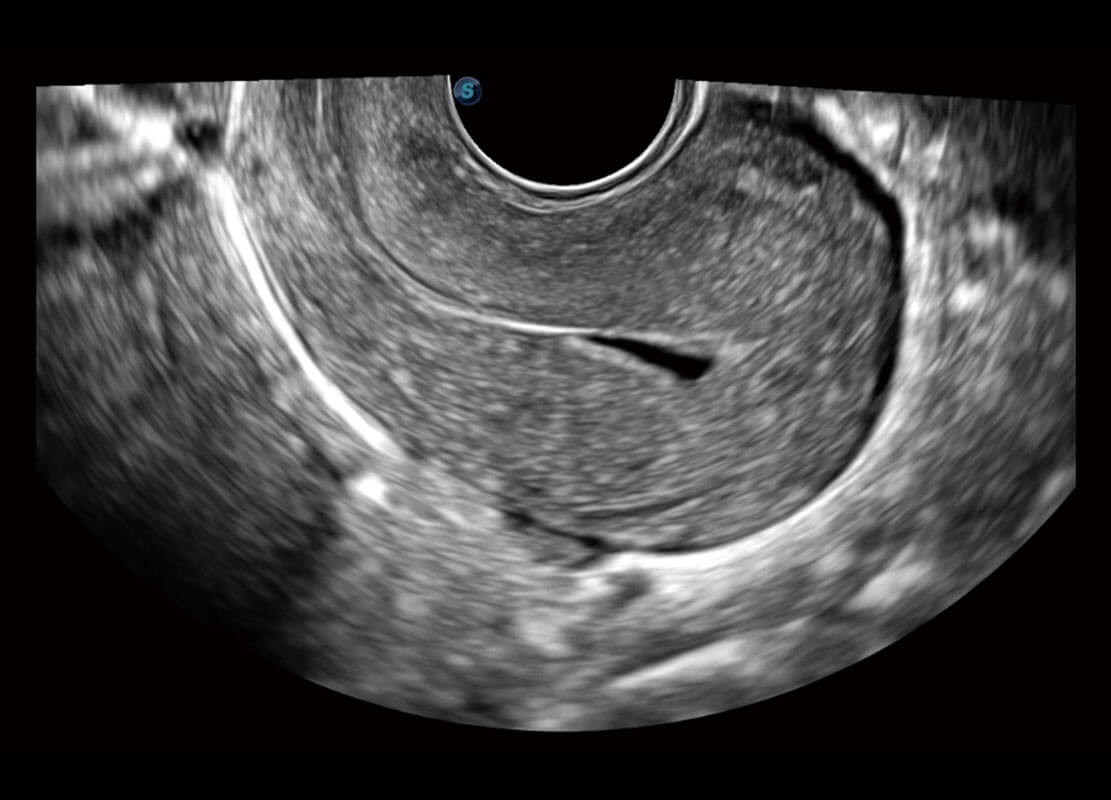

• 腔内三维-宫内节育器

• 腔内三维-光影成像

P60优异的图像质量搭载专科探头,在妇科基础疾病的诊断、卵泡生长的监测、输卵管通畅情况的判别等方面为您提供生殖应用方案。